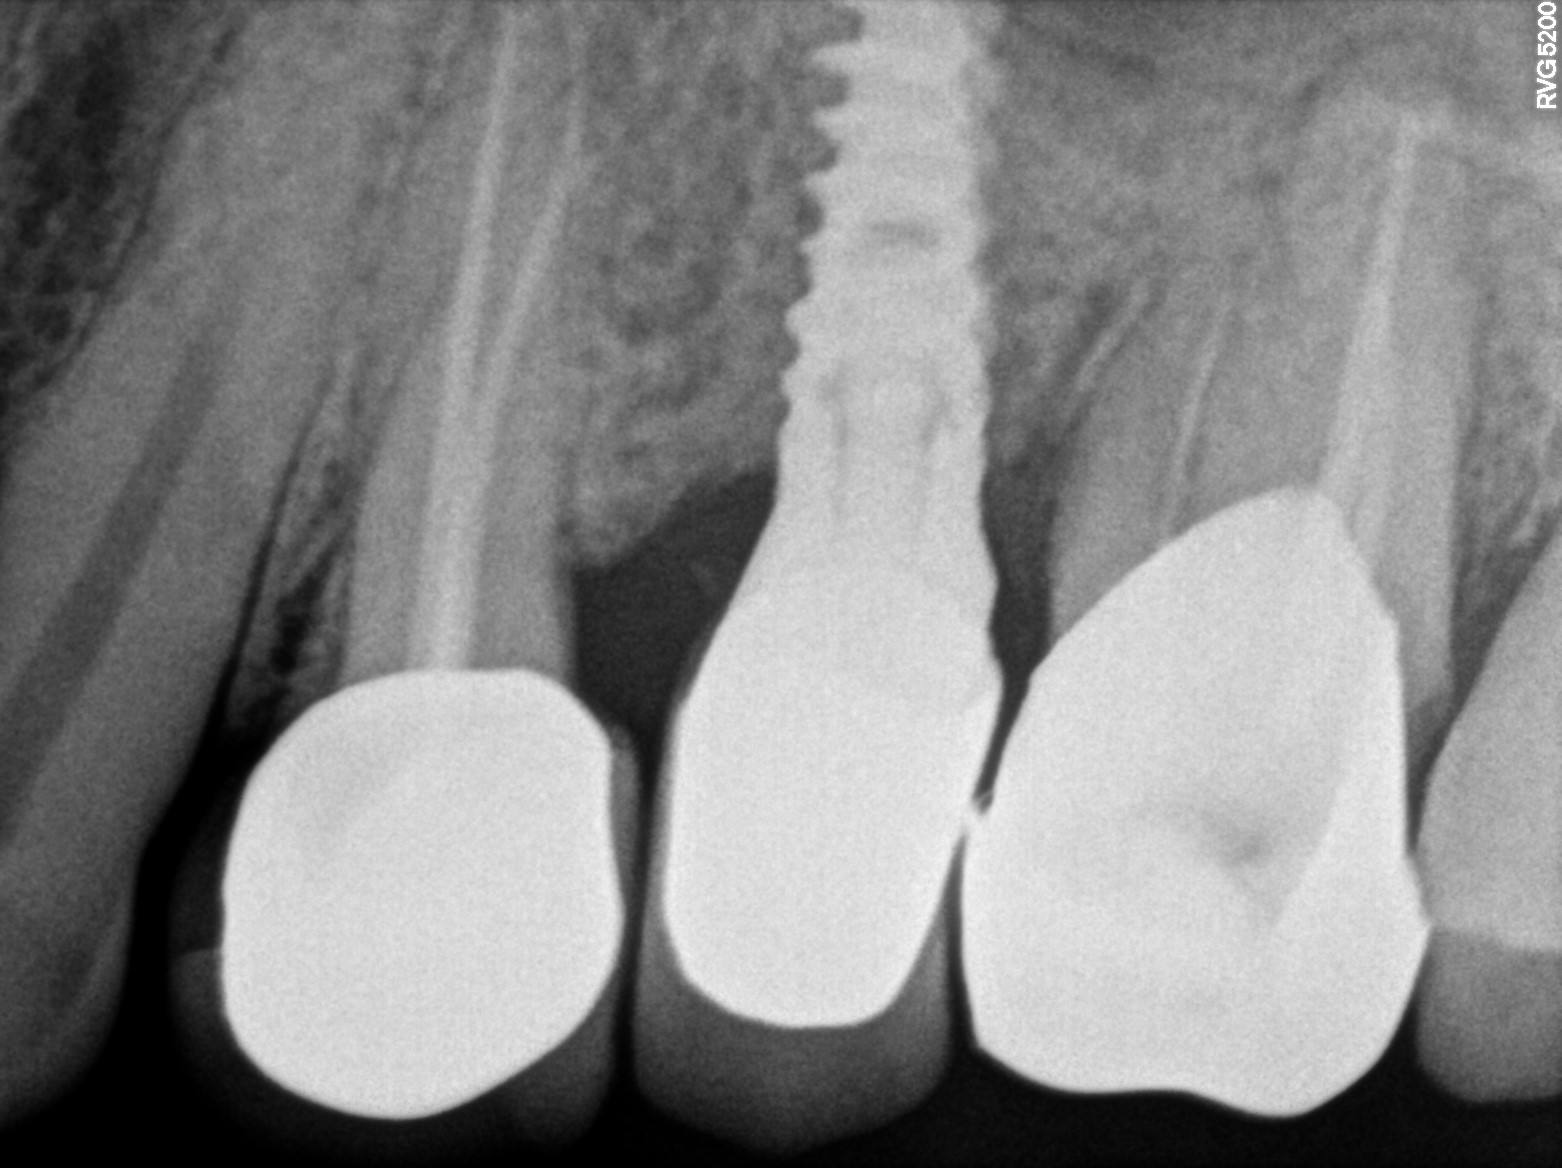

Dental Radiographs FHIR: DocumentReference · LOINC 24641-7

R55.jpg

24641-7